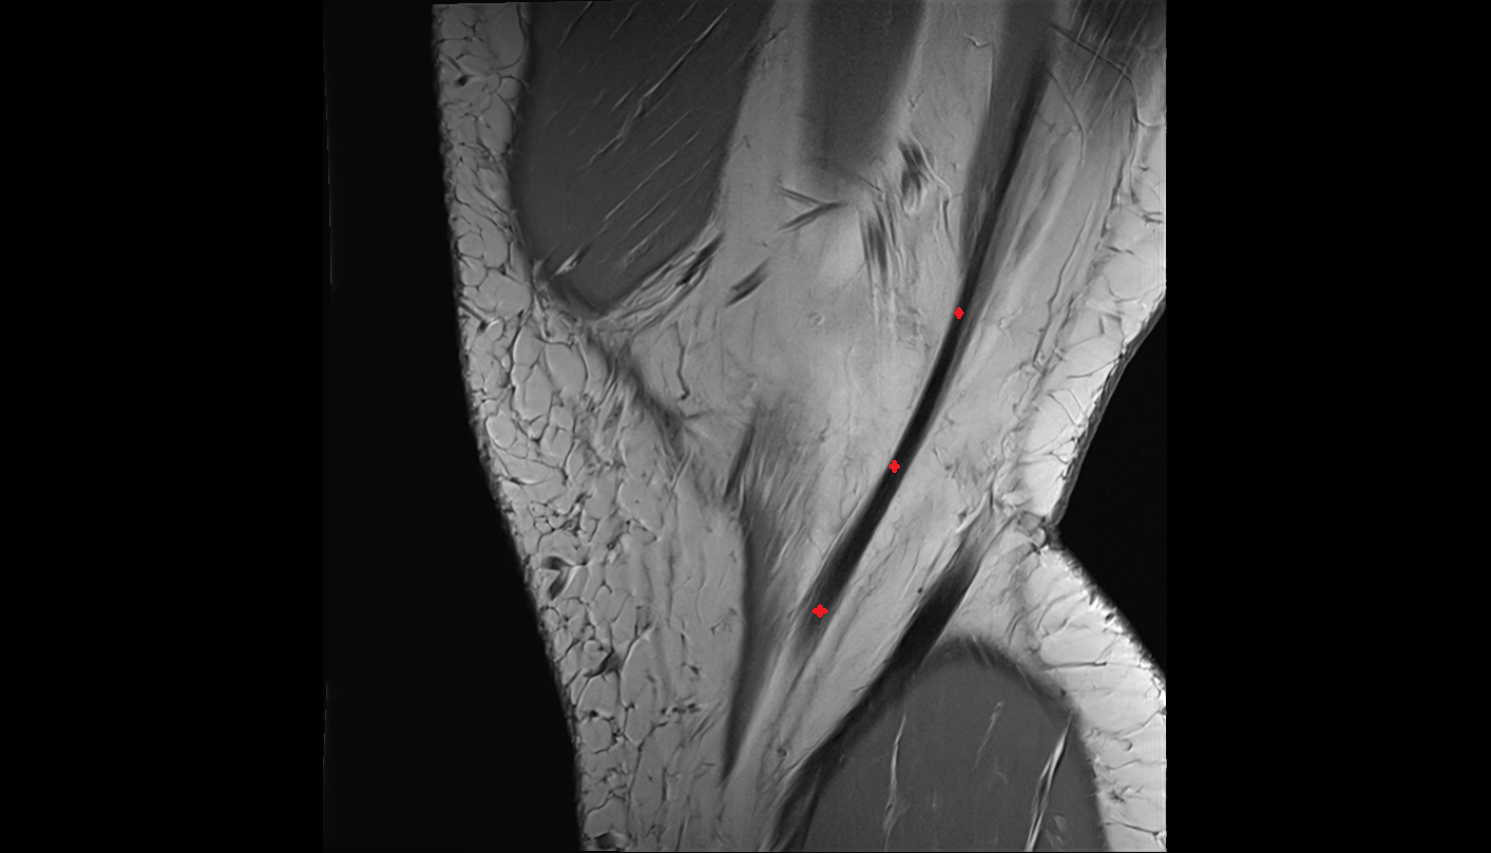

- Anterior cruciate ligament

- Posterior cruciate ligament